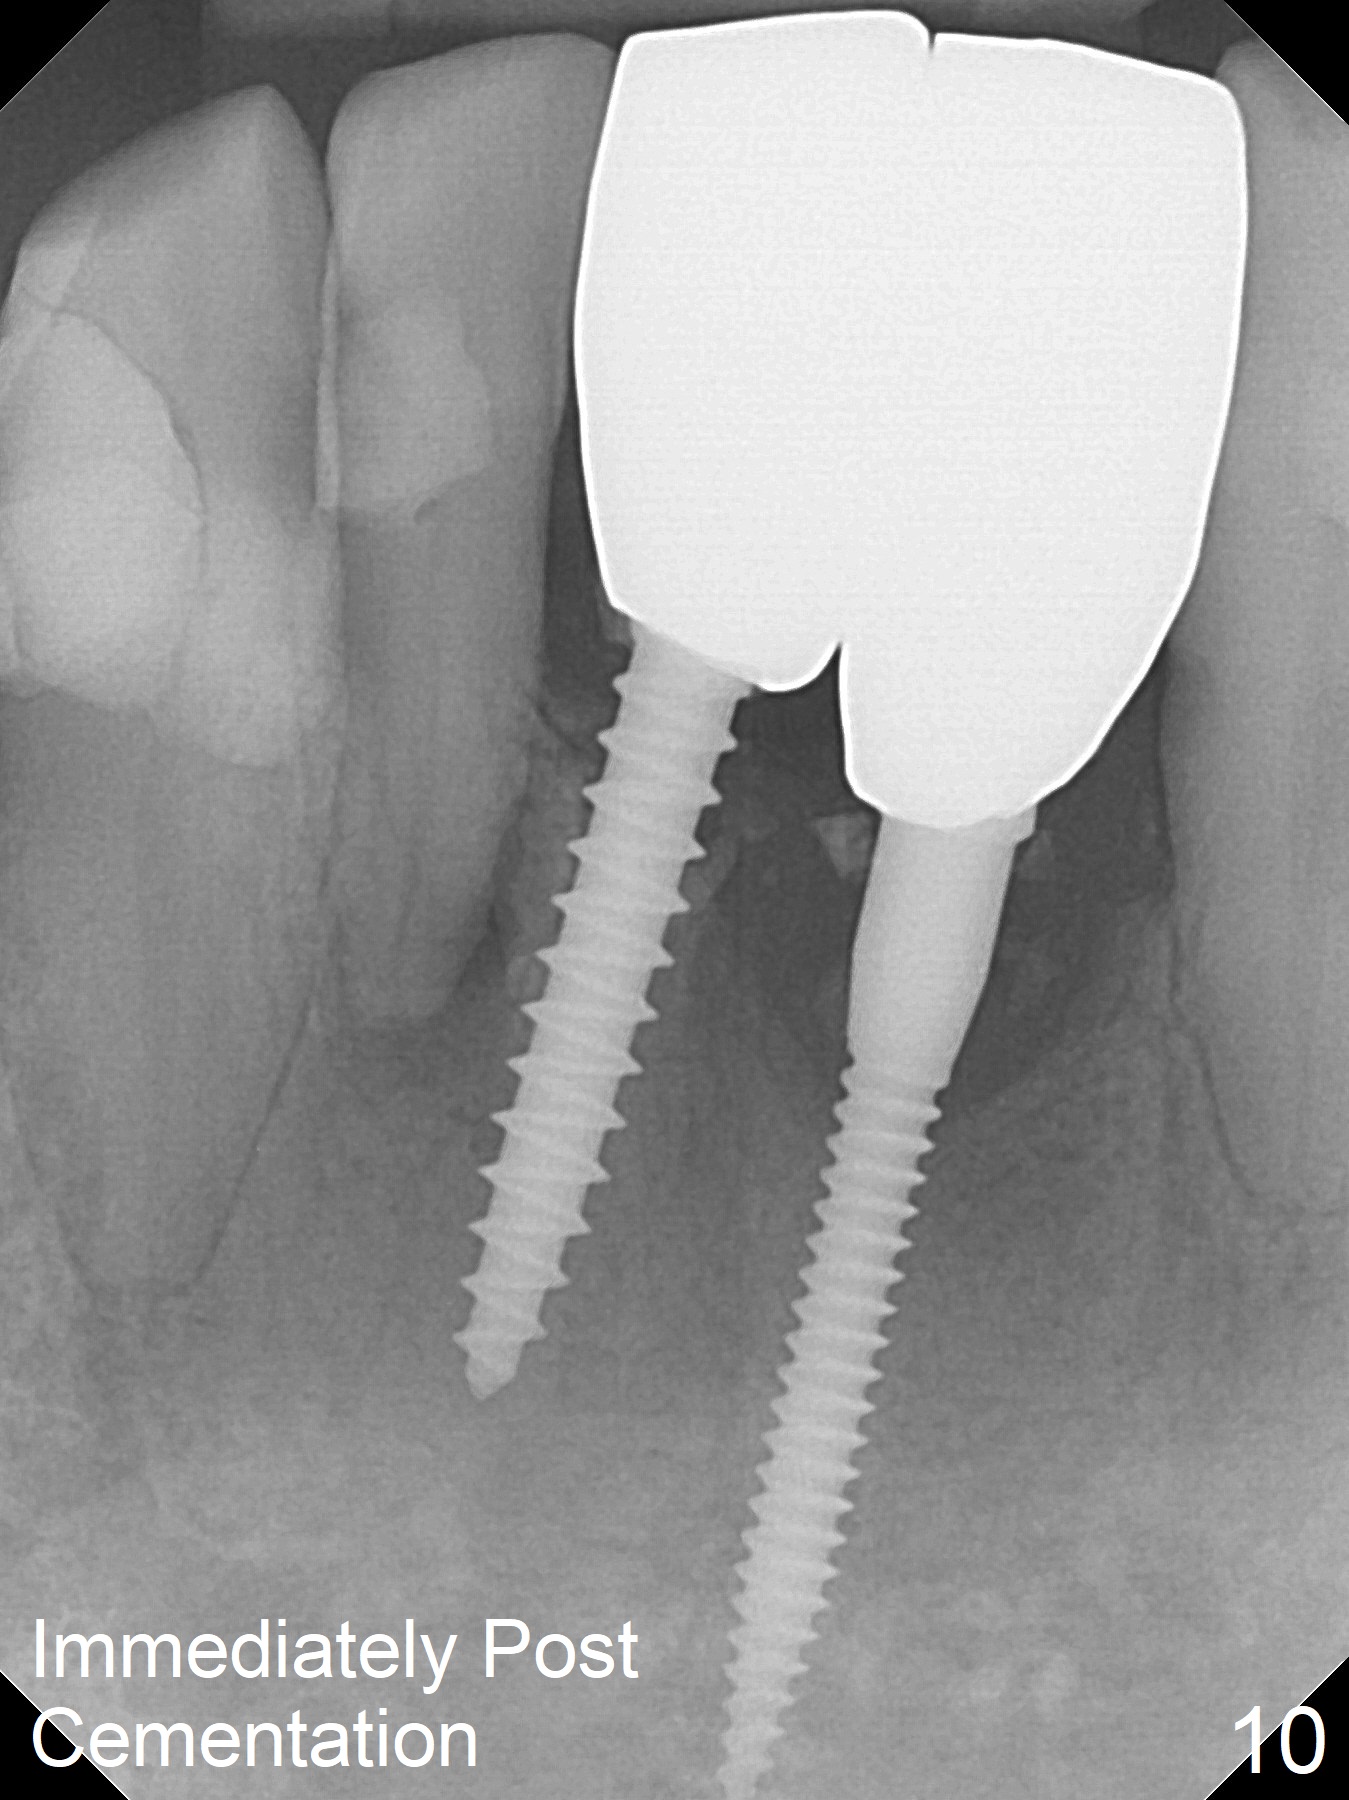

Two and a half months after loss of a 2 mm 1-piece approximately at #23 (Fig.1,2), it appears that the site of #24 (Fig.3 line) is more appropriate because the bone is higher. After removal of the pointed ridge top, osteotomy is initiated with 1.2 mm drill, followed by 1.5 mm one (Fig.4,5). When the 1.5 mm drill is removed, the new osteotomy (Fig.6 *) is mesial to the old one (^). Since the ridge is narrow (Fig.5,6), a 2x14(4) mm 1-piece implant is placed with GBR (Fig.7). Due to overprep, the torque is 20 Ncm. No immediate provisional is fabricated. Instead periodontal dressing is applied around these 2 implants. Two separate provisionals are fabricated when the wound heals. The one at #24 does not stay. The implant at #24 appears to osteointegrate 6.5 months postop (Fig.8). When the crowns are cemented, the margin is supragingival (Fig.9,10). Water Pik is recommended.